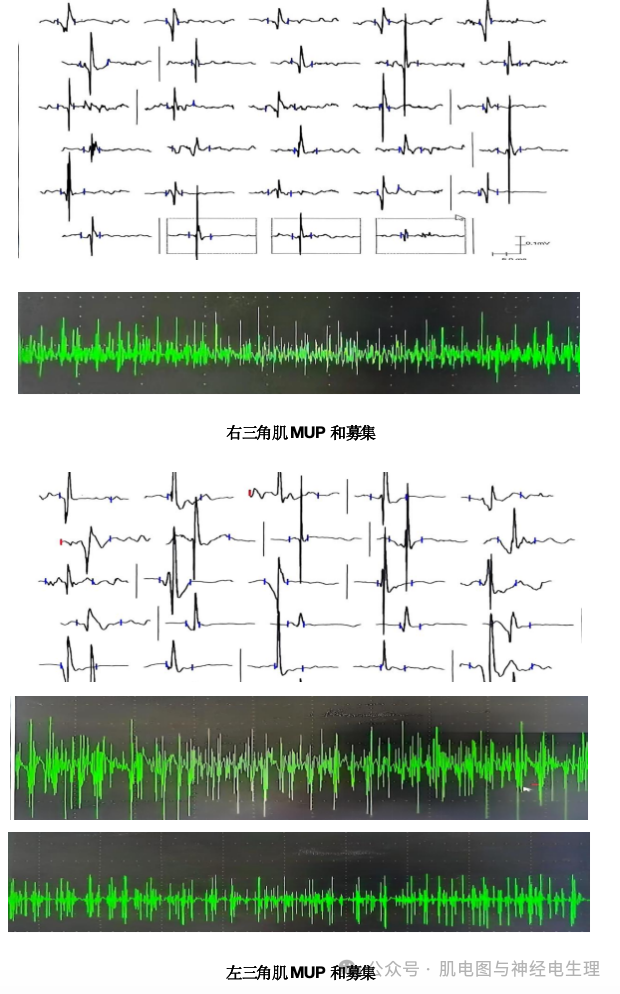

神经电生理检查结果

肌电图结论:

1.双侧肌皮神经、双侧腋神经运动传导异常之电生理表现;

2.双上肢呈肌源性损害之电生理表现。

神经电生理检查结果提示双侧肌皮神经、双侧腋神经运动传导潜伏期延长、波幅降低,考虑与患者双侧肱二头肌、双侧三角肌肌纤维丢失过多有关;其次,双上肢近端肌肉针电极肌电图检查结果提示肌源性损害,与患者临床表现、神经查体及神经传导检测结果相符,定性诊断考虑为面肩肱型肌营养不良。

4、电生理检查提示双侧肌皮神经、双侧腋神经运动传导潜伏期延长、波幅降低,且双上肢近端肌肉呈肌源性损害。